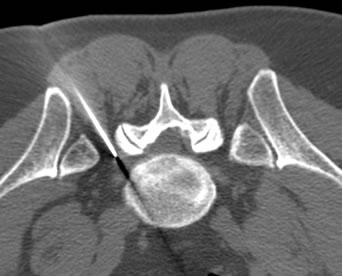

Il trattamento che noi pratichiamo prevede l’erogazione di radiofrequenza pulsata (RFP) e l’iniezione di cortisonico a lento rilascio. Con guida TC viene posizionato con accesso postero-laterale (per la sede toracica e lombare) o antero-laterale (per la sede cervicale) un ago da 22G (0,6mm) in prossimità del forame di coniugazione corrispondente; in questo ago, previa estrazione del mandrino, si inserisce coassialmente l’agoelettrodo; successivamente si posiziona sulla cute una piastra dispersiva per chiudere il circuito con il generatore di radiofrequenza. Si eroga quindi, previa stimolazione a 50 Hz, radiofrequenza pulsata a 2 Hz per sei/dieci minuti che consente di neuromodulare il ganglio della radice interessata. L'utilizzo della RFP consente di agire solo sulle fibre nocicettive del ganglio (evitando di ledere quelle motorie e sensitive) poiché alla punta dell'agoelettrodo, posizionata a qualche millimetro dal ganglio, si raggiunge una temperatura massima di 42° C. Sempre attraverso lo stesso ago, dopo aver estratto l’agoelettrodo, si iniettano 2-4 ml di steroide a lento rilascio. Dopo qualche minuto si asporta l’ago, si medica il piccolo foro cutaneo di ingresso, si appone un cerotto medicato e si toglie la piastra dispersiva. Il paziente viene tenuto in osservazione per 1-2 ore e poi riprende le sue normali attività.

Solitamente questa procedura viene eseguita monolateralmente ad un solo livello e dura complessivamente circa 30 minuti. Quando la sintomatologia è bilaterale o vi è il coinvolgimento di più radici è possibile eseguire il trattamento a più livelli nella stessa seduta.